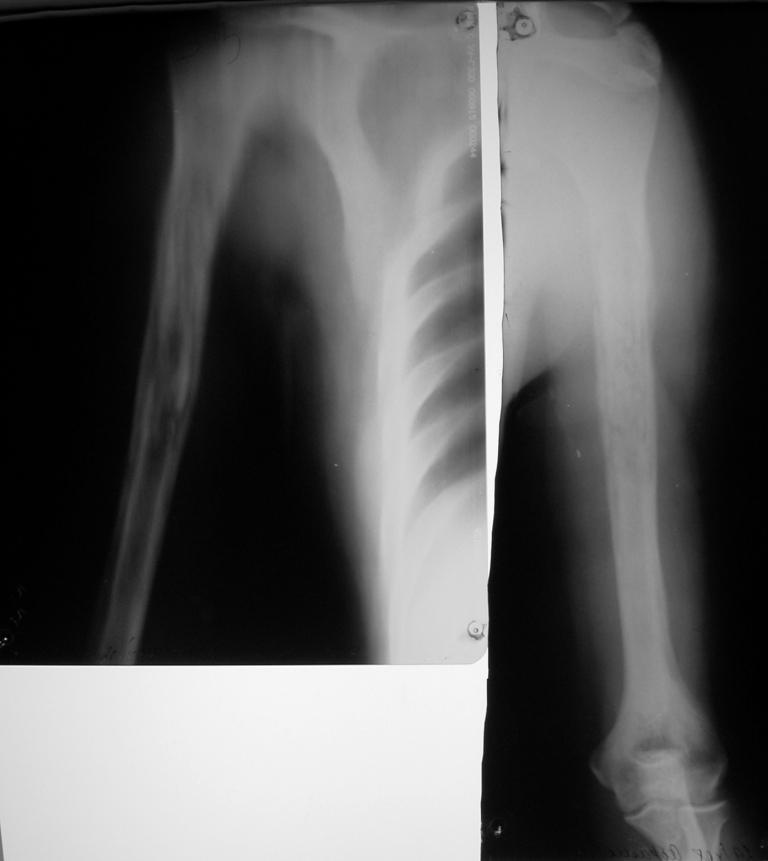

Остеомиелит плеча

Странно, вчера почему-то не увиделись рентгенснимки. Дифдиагноз с опухолью ИМХО должен быть на первом месте.

Секвестр средней, верхней трети плечевой кости четко виден на снимках - логичным подходом является секвестрэктомия , заполнение полости бусами с гентамицином, аппарат внешней фиксации. Перед началом хиургии сделайте посев свищевого отделяемого, непосредственно перед секвестрэктомией в операционной введите метиленовую синьку в свищевой ход и в процессе доступа к плечевой кости иссекайте прокрашенные ткани. По результату посева начинайте сАБ после хирургической обработки, длительность АБ курса

определяется по показателям СОЭ и С-реакт. белка. После контроля инфекции рассмотреть необходимость костной пластики, если Involucrum недостаточно

PS *рассверлить* секвестр и удалить его полностью из канала будет сопряжено с потерей неинфицированной кости проксимального идистального отделов плеча, поэтому предлагаю остановиться на открытой секвестрэктомии и иссечении инфицированного мягкотканного футляра.

Несмотря на прежнюю историю с инфицированием необходимо диагноз уточнить. Для доказательства хронического остеомиелита вместо фистулографии можно было бы сделать МРТ.

Она покажет процент вовлечения канала и отдифференцирует хронический процесс от метастаза.

подобная рентгеновская картина гематогенного остеомиелита, острый период которого прошел далеко не в сентябре, а много ранее, леченного активными антибиотиками нуждается в более подробном описании.Это ведь не вопрос-как оперировать, а суть в том, что никогда не знаешь сколько раз еще придется брать этого больного.Хотелось бы более полную информацию о пациенте, включая анализы крови, данные бакпосева, иммунного статуса.Согласен с д-ром Кульджановым о возможности МРТ, если у Вас есть кому эти данные интерпретировать.Необходимость внешней фиксации очевидна.О приготовлении спейсеров и бус с антибиотиками на данном форуме уже не раз писали.